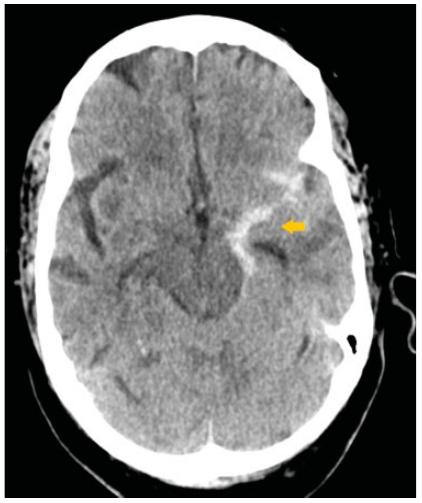

De nuestra serie de casos (n ¼ 228), solo se encontraron complicaciones en el 16,6%: hemorragias subaracnoideas secundarias a perforación (n ¼ 2) (►Fig. 1), hemorragia gangliobasal (n ¼ 1) (►Fig. 2), vasoespasmo (n ¼ 1), disección (n ¼ 1) (►Fig. 3), embolias (n ¼ 31) y pseudoaneurismas (n ¼ 2) (►Fig. 4) en el sitio de la punción. Cuando se detectó oclusión intracraneal (►Fig. 5), tras la trombectomía, dentro del grupo de las embolias, solo el 16,1% se presentaron hacia nuevo territorio vascular (arteria cerebral anterior) (►Fig. 6) o embolias distales. Debido al bajo número de complicaciones, se realizó un análisis mediante Fisher que da un resultado no significativo (►Tabla 3). Las hemorragias fueron subaracnoideas detectadas durante las trombectomías como la extravasación activa del contraste y corroborada mediante tomografía computada (TC) al finalizar el procedimiento. El vasoespasmo que se presentó fue moderado en arteria cerebral media izquierda que cedió tras la infusión intra-arterial de 0,2 mg nimodipino.

En tomografía computada de cráneo simple de control. La flecha señala ocupación del valle silviano izquierdo por contenido hemático posterior a trombectomía.